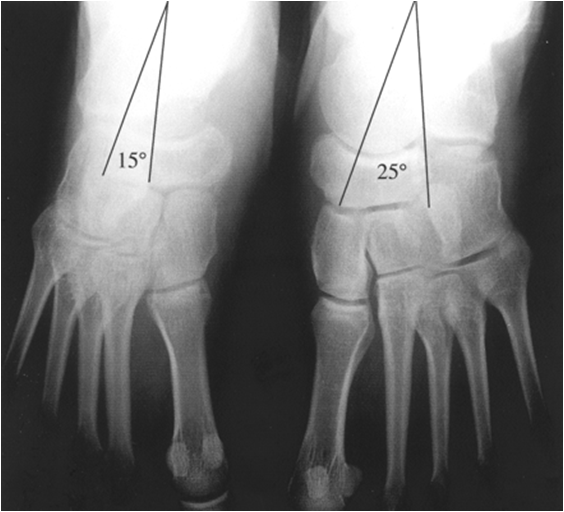

1 Radiographic Evaluation of the Pediatric Foot and its Deformities Amy Talipes Equinovarus Talus Clubfoot, also known as congenital talipes equinovarus, is a common idiopathic deformity of the foot that presents in neonates. Clubfoot, or congenital talipes equinovarus, is a complex deformity of the foot that affects the hindfoot, midfoot and forefoot. Clubfoot, also known as talipes equinovarus (tev), is a common foot abnormality, in which the foot points downward and inward. Clubfoot is. Talipes Equinovarus Talus.